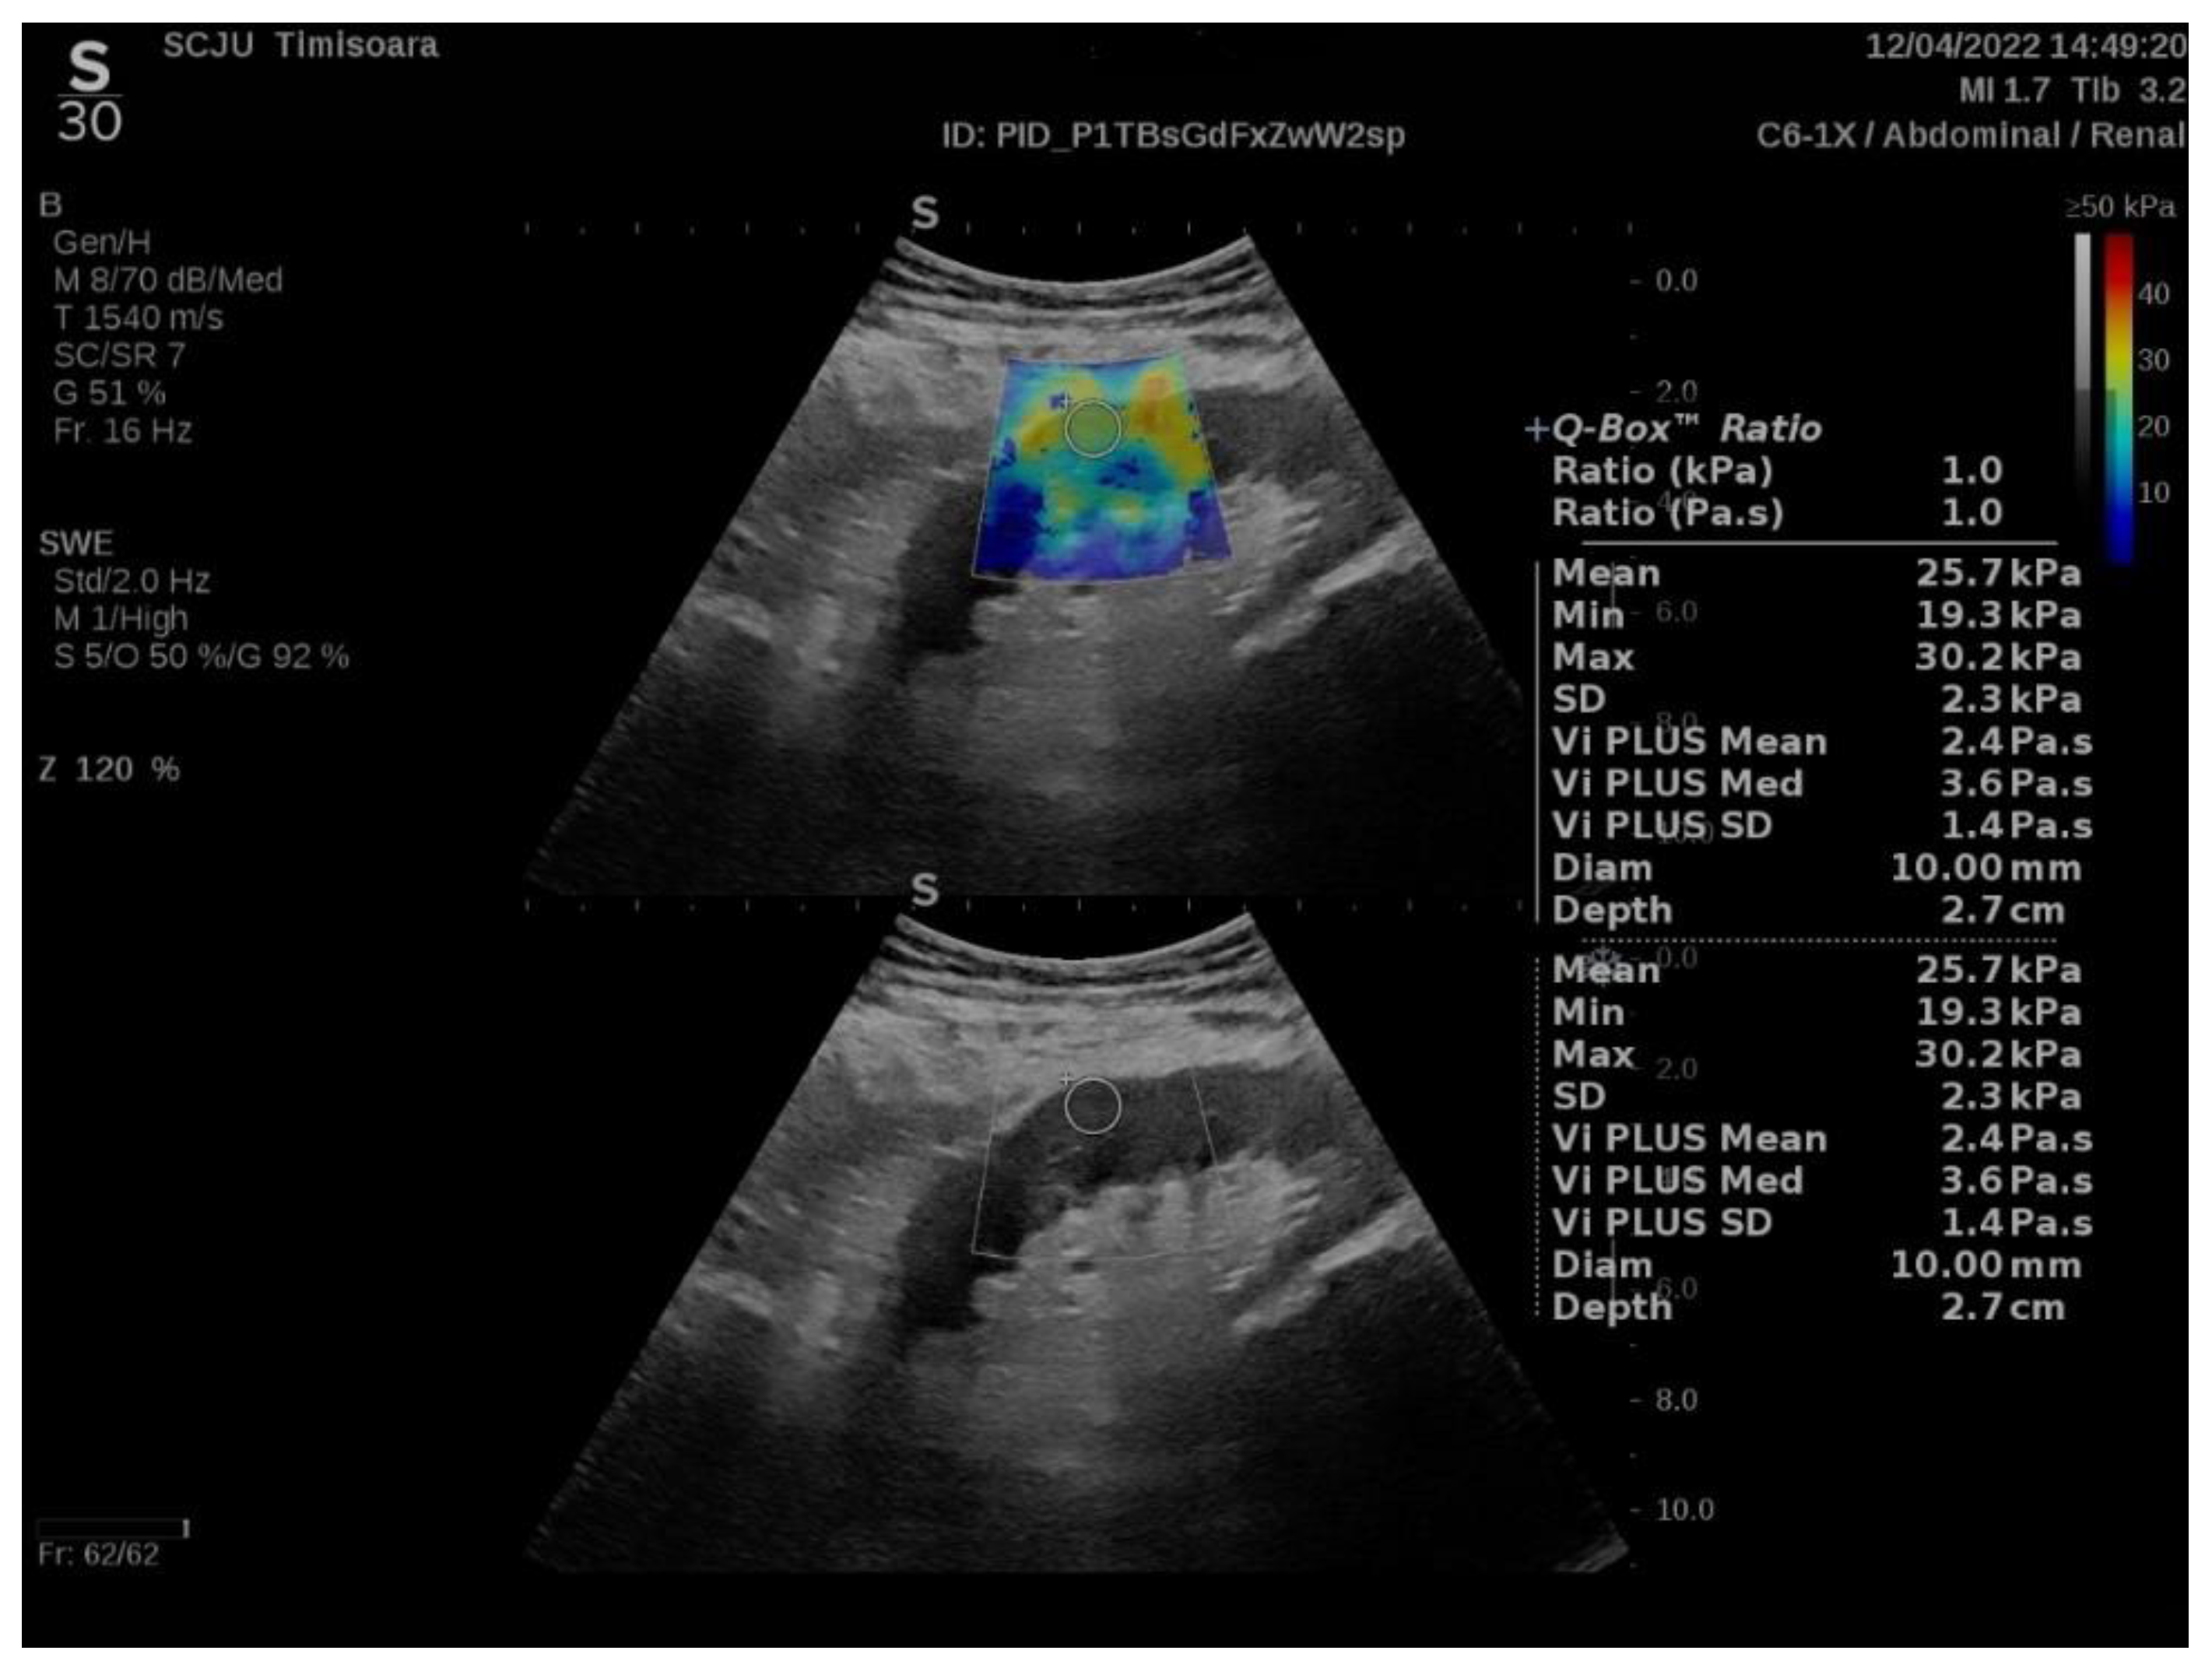

2.2. ShearWave PLUS Elastography